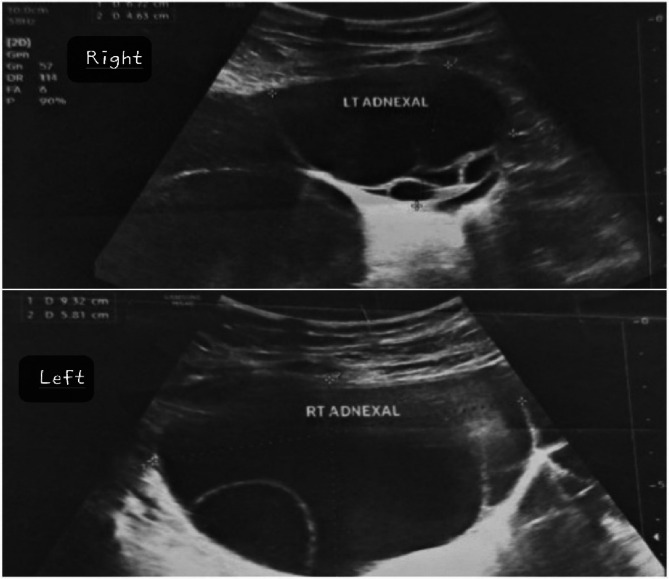

先天性甲状腺功能减退症(CH)是一种常见的疾病,如果不及时诊断和治疗,可导致婴儿显著的神经发育问题。Van Wyk和Grumbach综合征(VWGS)以甲状腺功能减退、性早熟和卵巢肿块为特征,由于诊断资源有限,在中低收入国家(LMICs)经常被误诊。这个病例强调了系统性的挑战,包括延迟诊断和不必要的手术转诊。我们报告一个8岁的女孩被诊断为Van Wyk-Grumbach综合征,其特征是严重的甲状腺功能减退,同性性早熟和卵巢过度刺激。她的症状包括阴道出血、腹胀和明显的肥胖并发育不良。检查显示严重甲状腺功能减退(TSH: 96 mU/L)和双侧卵巢囊肿增大。在开始左旋甲状腺素治疗后,患者表现出显著的临床改善,包括腹部肿胀减轻和甲状腺功能正常化。本病例强调了在儿童卵巢肿块鉴别诊断中考虑甲状腺功能减退的重要性,特别是在缺乏新生儿筛查方案的地区,以防止不必要的手术干预并确保对病情的适当管理。

Congenital hypothyroidism (CH) is a prevalent condition that can lead to significant neurodevelopmental issues in infants if not diagnosed and treated promptly. Van Wyk and Grumbach Syndrome (VWGS), characterized by hypothyroidism, precocious puberty, and ovarian masses, is often misdiagnosed in low- and middle-income countries (LMICs) due to limited diagnostic resources. This case highlights systemic challenges, including delayed diagnosis and unnecessary surgical referrals.We present an 8-year-old girl diagnosed with Van Wyk-Grumbach syndrome, characterized by severe hypothyroidism, isosexual precocious puberty, and ovarian hyperstimulation. She exhibited symptoms including vaginal bleeding, abdominal distention, and marked obesity with stunted growth. Investigations revealed severe hypothyroidism (TSH: 96 mU/L) and enlarged bilateral ovarian cysts. After initiating levothyroxine therapy, the patient demonstrated remarkable clinical improvement, including reduced abdominal swelling and normalizing thyroid function. This case underscores the importance of considering hypothyroidism in differential diagnoses of ovarian masses in children, especially in regions lacking newborn screening protocols, to prevent unnecessary surgical interventions and ensure appropriate management of the condition.